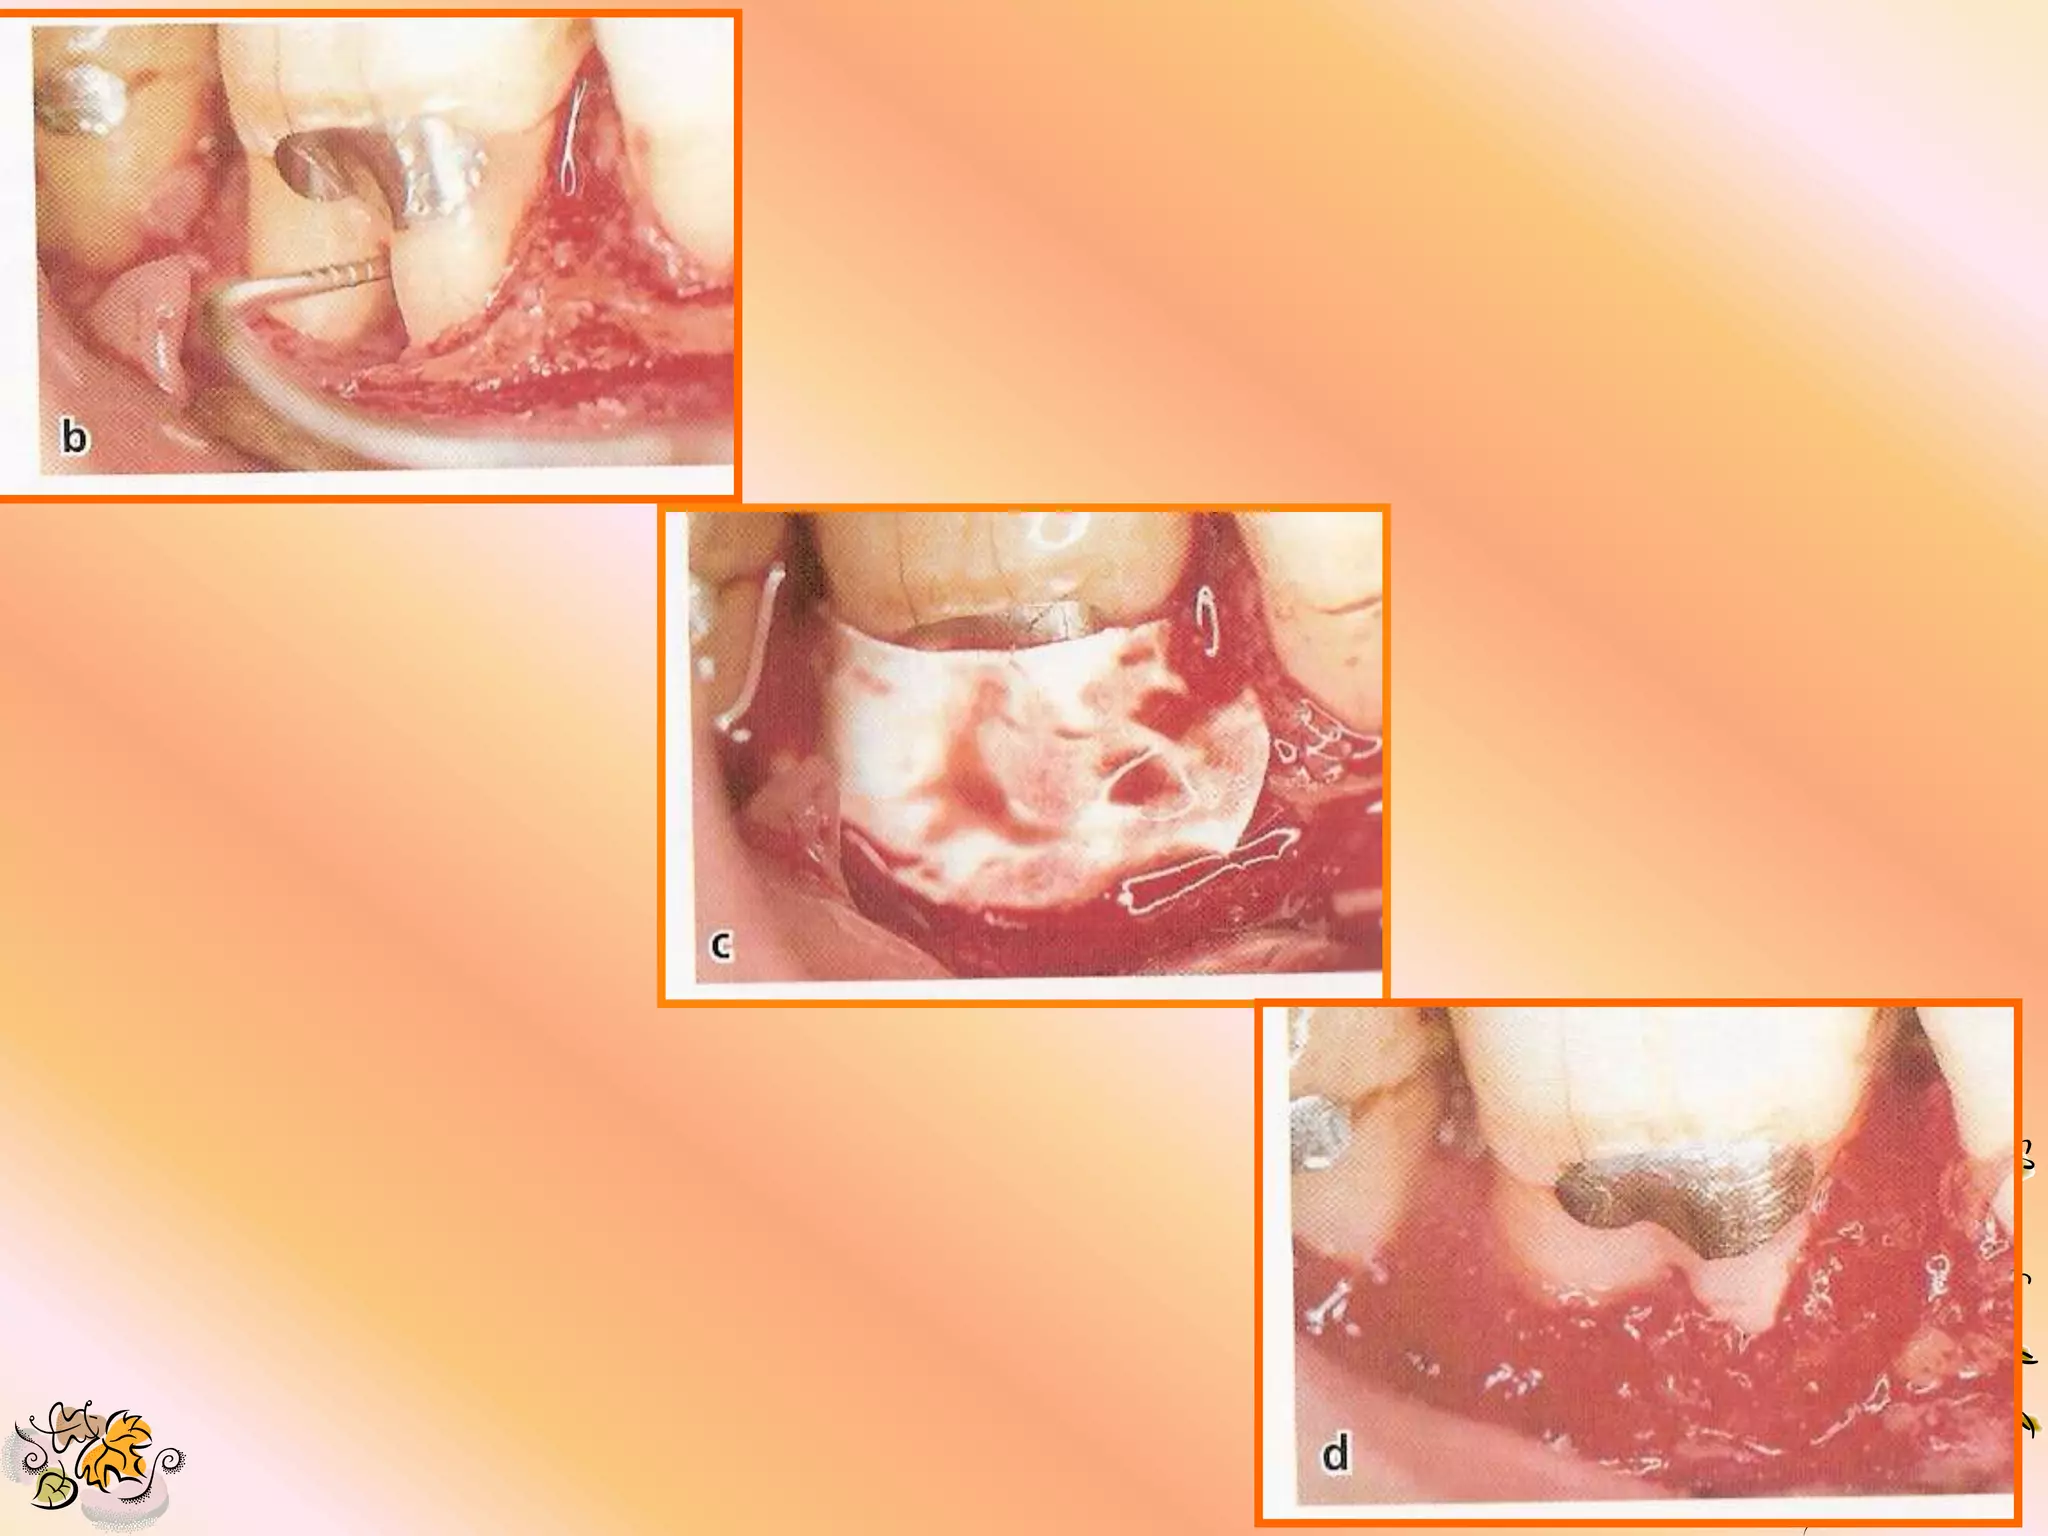

PRIMARY INCISIONS 1. Intra sulcular incisions are made in preparation for a full mucoperiosteal flap. 2. All residual pocket epithelium is removed after flap reflection to permit integration b/w the e-PTFE & flap connective tissue. 3. Incision should extend 1-2 teeth mesial &/ or distal of the area being treated to permit adequate visualization. 4. Vertical incision should be placed mesially where necessary.

DEFECT PREPARATION 1. Degranulationof defect. 2. Scaling & root planning for removal of all tooth deposits. 3. Decortification of bone for increased vascularity & scratching of the PDL to stimulate cell & vascular proliferation.

SELECTION & PLACEMENTOF GORE-TEX PERIODONTAL MATERIAL 1. Maintain sterility of material. 2. Choose a size that offers the most ideal design for defect coverage. 3. Shape the material with scissors, avoid leaving sharp edges.

4. Enough materialshould be left to permit lateral & interproximal suturing while leaving at least 3 mm apical & lateral overextension of defect margins. 5. Do not remove the open microstructure or coronal portion of the material. It can be trimmed on the lateral aspect. 6. The material should fit smoothly, avoiding folds, overlaps & protrusions which may compromise the overlying gingival tissue.

SUTURE MATERIAL 1. Gore-Tex suture (provided with material) is recommended for placing the material & flap closure. 2. Silk or monofilament suture may be used in areas away from the material. 3. Bioabsorbable sutures are not recommended.

SUTURING TECHNIQUES 1. Sling suture are used to approximate material over the defect without engaging the flap or tissue. 2. The material must fit tightly against the tooth surface at all points to prevent epithelial proliferation b/w tooth & material & to help in stabilizing the wound.

3. The flapmargin should ideally be 2 to 3 mm coronal to the material. 4. Tight flap apposition is desired to avoid premature flap opening & material exposure.